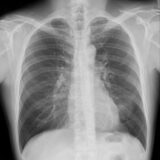

診断

COPDの診断には、呼吸機能検査(スパイロメトリー) が重要です。

息を勢いよく吐く検査で、1秒率(FEV1/FVC)<70%であれば閉塞性障害と判断します。

他には、以下の通り血液検査、画像検査などで評価します。

・胸部X線・CT検査:肺の過膨張や肺気腫の有無を確認。